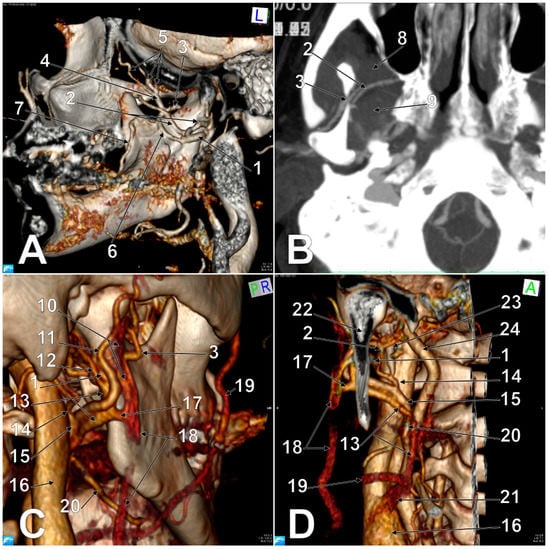

3.1. The First Variant of the ECV

3.2. The Second Variant of the ECV

3.3. The Third Variant of the ECV